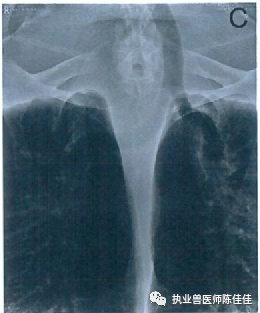

由于经口胃给予矿物油和促动力药物治疗并不能减少胃肠道扩张,因此决定尝试经壳肠穿刺术。海龟的左侧抬高至75°角,因此任何充满气体的肠段都将位于体腔的侧边缘。超声波检查用于识别腹甲中骨结构之间的软组织,从而可以引入20号5.1厘米的针头针头连接到延长线,三通旋塞和60毫升注射器上。将针头通过左侧第三下边缘外侧的结缔组织插入肠腔(图2)。排出约10.3升气体,无并发症随访的X放射图显示,先前压缩的左肺以及位于体腔腹侧底部的肠袢的扩张和轮廓接近正常(图3)。海龟被放回水中,并立即在水面出现中性浮力。那天晚上晚些时候,它能够保持在水下,并被观察到舒适地躺在水箱底部。肠穿刺术三天后,大量粪便含有带血的粘液和约250毫升凝胶状胃肠道脱落组织排出。对该组织的显微镜检查显示坏死的上皮细胞。在此事件发生后,海龟继续排出正常的粪便,随后的超声波检查显示正常的胃肠道循环和摄入。结肠也看起来正常,没有气体膨胀或嵌塞的迹象。尽管浮力障碍已在临床上得到解决,但该动物仍住院了152天,以控制双侧肺炎。在此期间,海龟被维持在前面提到的抗生素治疗方案中,直到临床症状和血液检查允许医疗许可释放。在剩余的住院期间没有发现进一步的并发症;因此,确定该动物已准备好释放,并且不太可能再次出现气体膨胀。

图:2。图中显示了红海龟在经壳小肠穿刺术中的位置。箭头表示插入针头以从胃肠道排出气体的解剖学标志。照片来源:Melanie Lemieux。